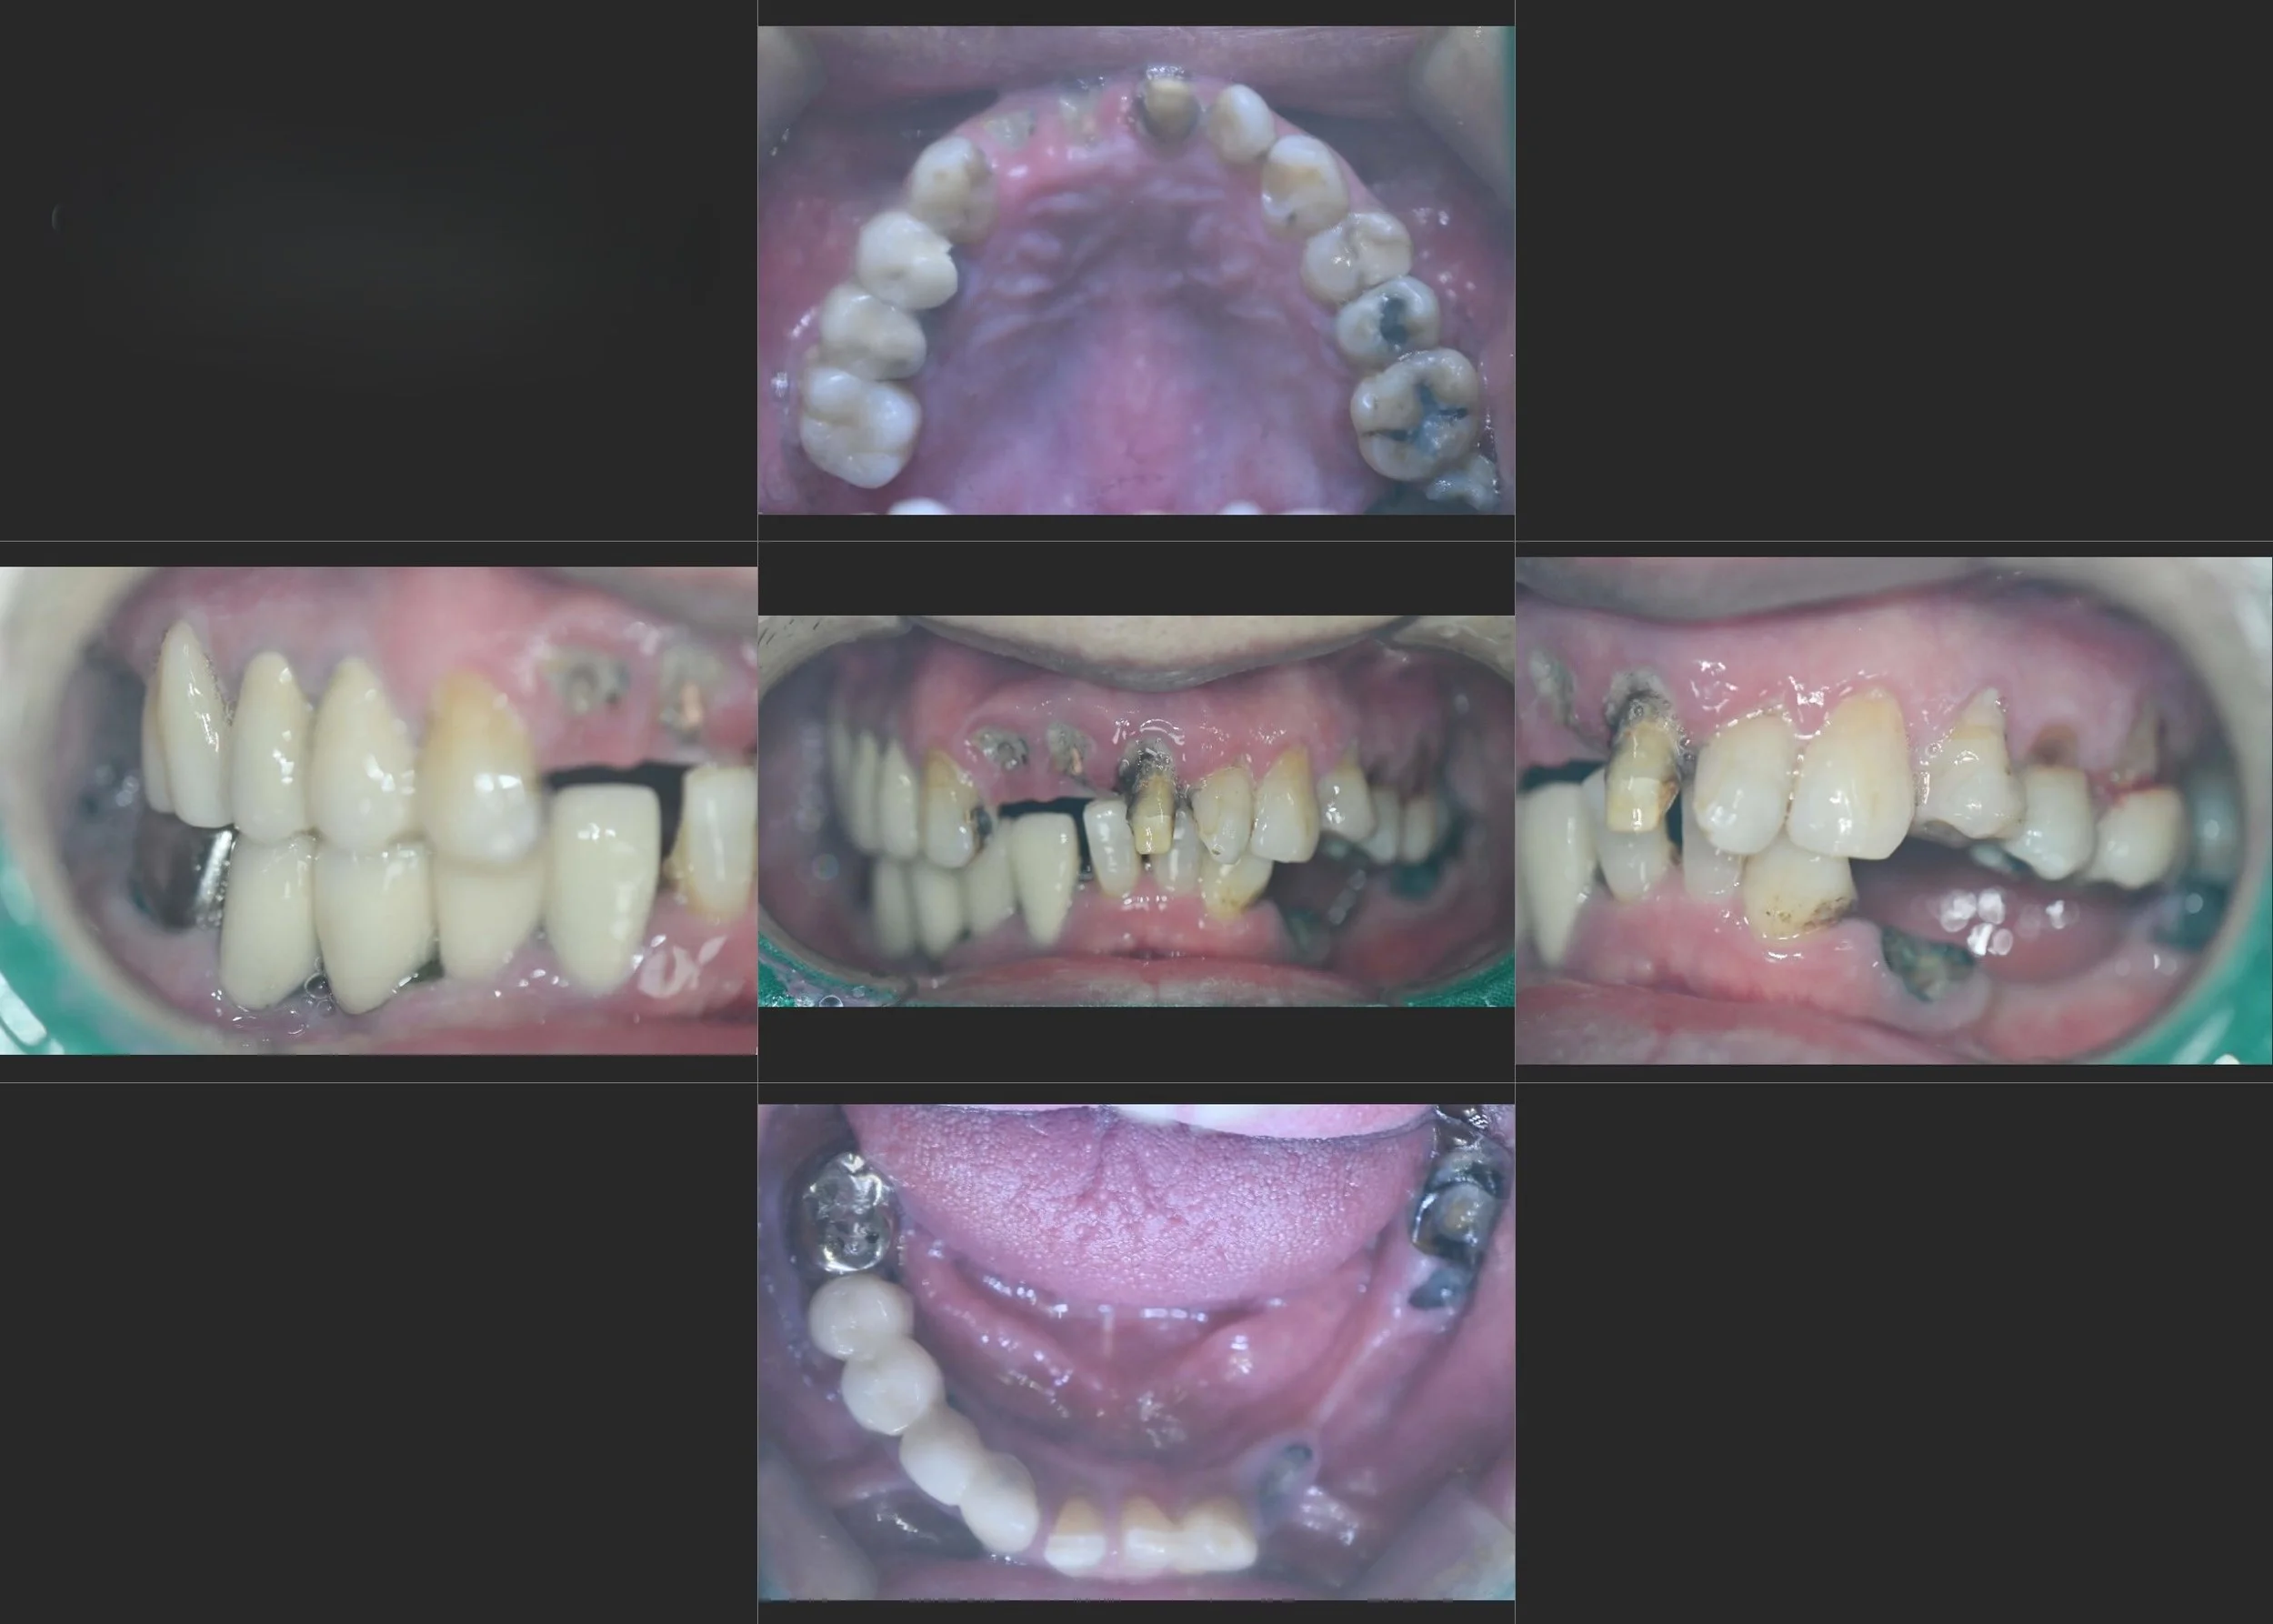

INTRA ORAL - BEFORE

The patient presented with a collapsed occlusion and mandibular instability,

associated with long-standing unilateral mastication and facial asymmetry.